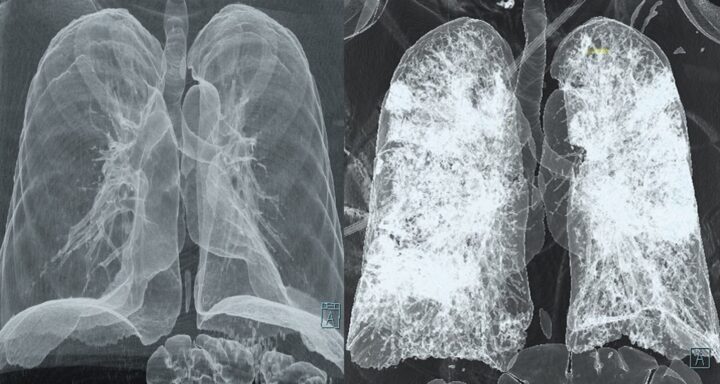

In Italia sono stati persi 60 mila ettari di bosco negli incendi che si sono sviluppati in Sardegna, Sicilia, Lazio, Marche e Abruzzo. Purtroppo i roghi, di entità perfino superiore, hanno interessato anche altri Paesi, in Turchia e Canada sono bruciati 140 mila e 200 mila ettari di foreste con un incremento delle emissioni di CO2 annua del 17%. Ci sono prove evidenti che gli incendi hanno amplificato l’effetto dell’esposizione a breve termine al PM2,5 sui casi e sui decessi di Covid-19. È stato tutto raccolto nello studio portato avanti dall’Università di Harvard e pubblicato su Science Advances. Eravamo già a conoscenza del ruolo dell’inquinamento sull’andamento della pandemia da Sars-CoV-2, ma i nuovi dati ci dovrebbero far riflettere, soprattutto dopo l’estate di fuoco che ha interessato metà della penisola. Già in altri studi si era dimostrato che l’esposizione a PM2,5 specifica per incendi boschivi a breve termine è collegata all’aumento dei sintomi dell’asma e ricoveri ospedalieri per problemi respiratori, nonché all’incremento del rischio di contrarre infezioni virali respiratorie. La causa è chiaramente il particolato fine presente nel fumo, capace di irritare i polmoni, causando infiammazione e influenzando il sistema immunitario. Ciò rende l’organismo più incline ad infezioni polmonari, incluso il Covid-19. L’incremento di 10 microgrammi di PM2,5 per metro cubo di aria in 28 giorni ha causato la crescita dell’11,7% dei casi e un +52,8% dei decessi.

Con il termine particolato si indica la miscela di particelle solide e liquide provenienti da sostanze organiche ed inorganiche sospese in aria, questa miscela forma quello che viene detto aerosol atmosferico. Queste sostanze possono essere di origine naturale o associate all’attività antropica. È sicuramente il maggior inquinante delle aree urbane. Il particolato è suddiviso in base alle dimensioni, che variano da pochi nanometri a 100 µm, abbiamo quindi un PM10 e un PM2,5. PM10 con diametro aerodinamico inferiore a 10 µm, in grado di penetrare nel tratto superiore dell’apparato respiratorio. PM2,5 con diametro aerodinamico inferiore a 2.5 µm, in grado di raggiungere i polmoni ed i bronchi secondari. Nel mese di gennaio dello scorso anno erano ben cinque le città italiane che sforavano di 18 volte i limiti giornalieri di PM10, le città in questione erano Frosinone, Milano, Padova, Torino e Treviso. Il Ministero della salute ha dichiarato che ogni anno 30 mila decessi in Italia sono collegati al particolato fine PM2,5 presente nell’aria. Mediamente l’inquinamento atmosferico riduce di 10 mesi la vita di ogni cittadino italiano. L’Organizzazione Mondiale della Sanità consiglia come soglia per la protezione della salute umana un valore medio annuo pari a 20 µg/m3 per il PM10 e a 10 µg/m3 per il PM2.5, ma non esiste un livello sotto il quale l’esposizione allo smog possa essere considerata “sicura”.

CONSEGUENZE SULL’ORGANISMO

L’Agenzia internazionale per la ricerca sul cancro (IARC) e l’Organizzazione mondiale della sanità (OMS) hanno classificato il particolato come carcinogeno di classe 1, ovvero in grado di causare tumori o favorirne l’insorgenza e la propagazione. I danni provocati dal particolato sono da ricondursi anche alla sua composizione, ovvero presenza o meno di metalli pesanti e idrocarburi. Come succede per la maggior parte degli inquinanti è la dose che fa il veleno, un’esposizione prolungata contribuisce al rischio di sviluppare malattie cardiovascolari, polmonari ostruttive croniche o infezioni acute delle basse vie respiratorie. Comunemente si pensa che all’inquinamento aereo siano collegati esclusivamente problemi ai polmoni, ma ad esso sono connesse molte altre patologie, come ictus, ischemie, malattie renali, demenza, diabete e rischi in gravidanza. Le nanoparticelle possono essere inalate, dai polmoni passare al circolo sanguigno e da qui a ogni distretto del corpo, accumulandosi negli organi. Anche concentrazioni moderate di PM2,5 comportano un serio rischio dell’aumento di un arresto cardiaco non ospedaliero, al quale sopravvive un paziente su 10. Per aggiungere un altro punto alla lista dei motivi per smettere di fumare vorrei far presente che il particolato fine è 10 volte maggiore nelle case dei fumatori, e un non fumatore che abita con un fumatore inala la stessa quantità di PM2,5 di un non fumatore che vive a Pechino.